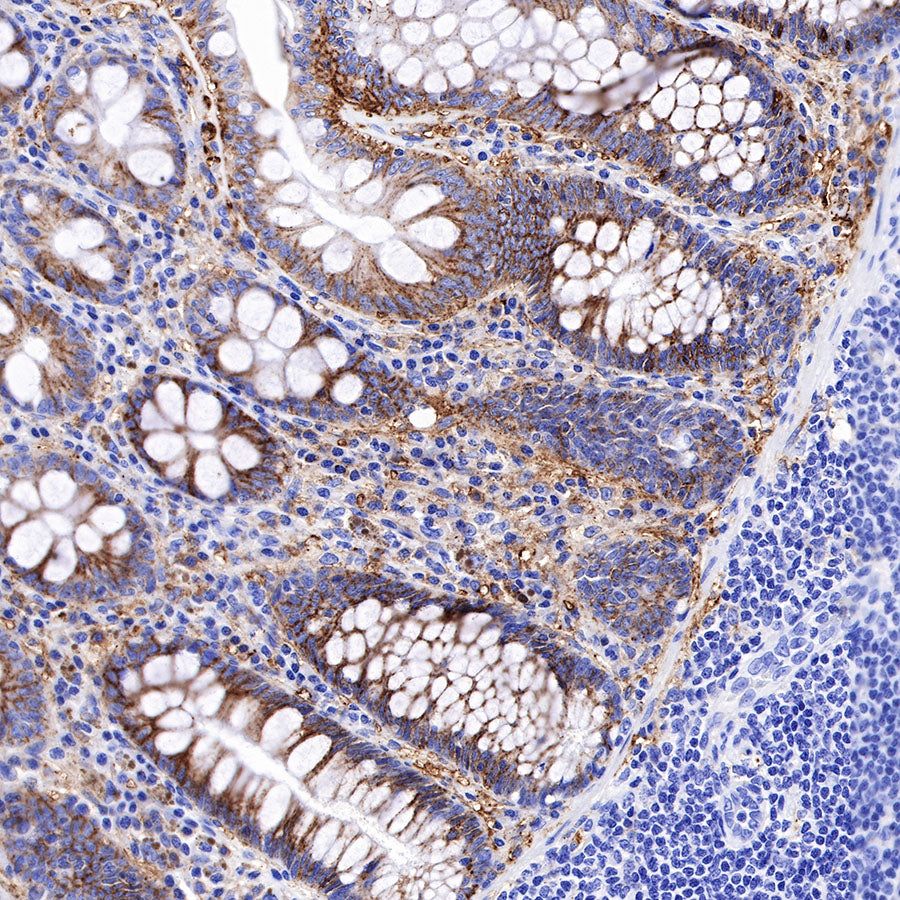

Syndecan-1 (CD138) is mostly restricted to epithelia, and bears heparan sulfate chains that are capable of interacting with a large array of polypeptides, including extracellular matrix components and potent mediators of proliferation, adhesion and migration. For this reason, it has been studied extensively with respect to carcinomas and tumor progression. Frequently, but not always, syndecan-1 levels decrease as tumor grade, stage and invasiveness and dedifferentiation increase. However, in some tumors, levels of syndecan-1 increase, but the characterization of its distribution is relevant. There can be loss of membrane staining, but acquisition of cytoplasmic and/or nuclear staining that is abnormal. Moreover, the appearance of syndecan-1 in the tumor stroma, either associated with its cellular component or the collagenous matrix, is nearly always a sign of poor prognosis [PMID: 33921767].

Picture

Immunohistochemistry